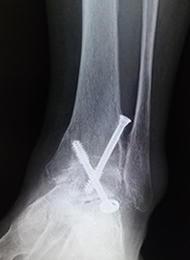

変形性足関節症

変形性足関節症は、足関節の表面に覆われている軟骨がすり減ってしまう疾患です。骨折や繰り返す捻挫など外傷によって起こることが多いと言われています。歩行時に軟骨のすり減っている部分に疼痛が生じます。また病態が進行すると、外観上も足の変形が認められます。

変形の程度が軽い場合は、足底挿板や鎮痛薬内服による治療を行います。痛みが強い場合や変形が強い場合は、主に関節固定術を行います。適応となる患者さんは限られていますが、足関節の可動域を温存するため、脛骨低位骨切り術や人工足関節置換術を行うこともあります。

当院では、膝関節や股関節などの下肢全体のアライメントを含めて、痛みの原因を追究し、手術療法を決めるようにしています。従来は足関節前方を大きく切開して行う方法が行われていましたが、手術後の痛みや傷が大きくなることが問題でした。当院では患者さんへの侵襲を減らすため、皮膚切開を大きく行わない関節鏡視下関節固定術を積極的に導入しています。

![]() 変形性足関節症の 単純レントゲン写真 |

![]() 鏡視下固定術術後 |